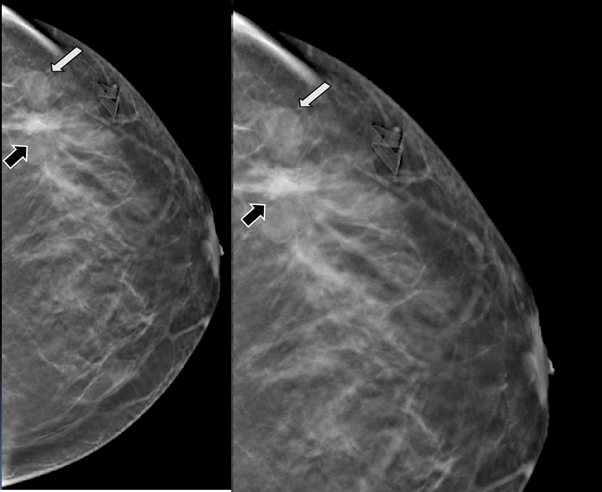

Figure 3 Digital breast tomosynthesis (DBT) in MLO projection. The margins of the nodule are well defined (white arrow) and the architectural distortion is confirmed (black arrow).

Figure 4 Digital breast tomosynthesis (DBT) in CC projection. The margins of the nodule are well defined (white arrow) and the architectural distortion is confirmed (black arrow).